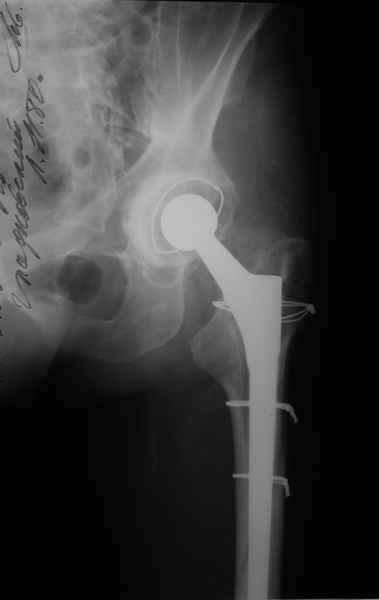

2. Применение ножки дистальной фиксации, мы отдаем предпочтение ножке Вагнера с фиксацией проксимального отдела на ножке. Более травматичное вмешательство, но при стабильной фиксации ножки реабилитация идет в обычном режиме.

Хочется показать два подобных случая, П-ка З. 72 лет и п-т Г. 80 лет. Сразу принимаю замечание, что это были ножки цементной фиксации, просто под руками не было бесцементника.

Пациента удалось осмотреть недавно. Достигнутый результат сохраняется. Перелом бедра сросся. Конечность опорная и безболезненная, ходит без трости. Ножка, похоже, реинтегрировалась, как и надеялись. Снимки и фото в приложении. Комментарии приветствуются.

Надо ли что-то делать дальше, как полагаете? Убрать винты? Убрать "удлинитель ножки"? Или оставить все, как есть? Спасибо заранее.